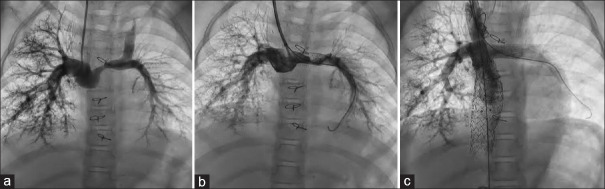

Background: Branch pulmonary artery (PA) stenosis must be addressed early to prevent right ventricular scarring and establish lung blood flow. Balloon-mounted stents are more useful in managing right ventricular outflow tract (RVOT) obstruction and PA stenosis.

Materials and methods: We studied the clinical and angiographic data of children with congenital heart disease who underwent stenting for RVOT obstruction and branch PA stenosis using the Formula stent (Cook Medical, Limerick, Ireland) between 2018 and 2024 in a tertiary pediatric cardiac center in southern India.

Results: Our patient cohort included 65 patients with a median age of 3 years (range: 3 months to 17 years). The median weight of patients was 11.5 kg (4.8-60.4 kg), with 40% weighing <10 kg. Out of the 87 stents implanted, four stents were implanted in RVOT, while the rest were branch PA stenting. The median stent length was 20 mm (12-60 mm), and the median stent diameter was 10 mm (5-10 mm). All stents were deployed using 5Fr to 8Fr sheaths or guiding catheters. The median procedure time was 62 min (20-170 min), with a median fluoroscopy time of 15 min (4-110 min). A total of 17 (19%) stents in 14 patients required further dilatation at a mean interval of 25 ± 4 months from the time of stenting. Ballooning resulted in an increase in diameter from 7.8 ± 2.2 mm to 10.2 ± 1.7 mm. Right ventricular systolic pressure had reduced from 70.3 ± 8 to 40.1 ± 1 mmHg after balloon dilatation in patients with a biventricular heart.

Conclusion: The Formula stent provides a comprehensive stent size option, requiring smaller sheaths, reduced procedural time, minimum complications, and an acceptable rate of reinterventions.